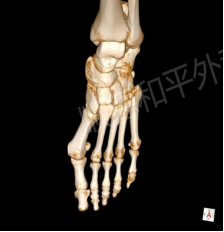

所幸摄片时发现关节面对合关系尚可,所及诸骨骨质结构完整,骨纹理连续,未见明确骨折或骨质破坏,各关节在位,关节间隙清晰。仅需行左足拇外翻微创截骨矫形内固定即可。

手术过程中,先测量、纠正拇外翻的角度(外翻角约33°),于大脚趾外侧做一个小小的切口,从第1跖骨底部做一个“三角形”截骨,调整“长歪”的第1跖骨的角度和长度,再用螺钉最终将第1跖骨和跖骨头“固定”在一起,以保证手术矫正的效果。